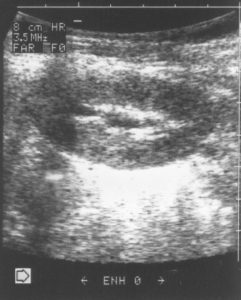

Фиг. 2. а/ – Пиелектазия – незначително отслояване на стените на бъбречното легенче, надлъжен срез и б/ Пиелектазия – напречен разрез на легенчето с предно-заден размер на дилатацията до 5 мм.

Специално прилагам УЗ образ /Фиг.2/ на това установено в УЗ образ на бъбреците при кърмачета отклонение, защото то е често срещано, но много рядко налага допълнителни изследвания.

Особено внимание ще отделя това най-често „малко” отклонение с наличие на незначително количество урина в пиелона – пиелектазия /Фиг.2/.